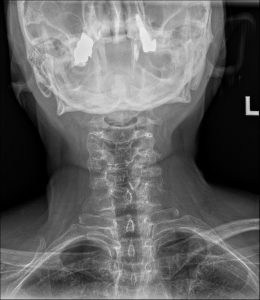

To investigate the underlying cause of her disproportionate response to a minor trauma, a standard three-view cervical spine radiographic series was ordered. The images provided a clear and immediate explanation for her clinical presentation.

On the lateral cervical view, the most striking finding is a congenital failure of segmentation involving the C6 and C7 vertebral bodies, their posterior articular pillars, and the corresponding spinous processes. This osseous fusion creates a single, solid block. At the anterior margin of this C6-C7 block, a distinct concavity or indentation is present at the level of the rudimentary disc. This feature, known as the “wasp-waist” sign, is a pathognomonic indicator of the congenital nature of the fusion.

The diagnostic story, however, does not end with the block vertebra itself. The true source of her pain and dysfunction is revealed at the adjacent motion segment above the block. The C5-C6 level demonstrates moderate to advanced degenerative changes. There is significant anterior osteophyte formation, marked narrowing of the intervertebral disc space, and notable facet arthrosis with sclerosis of the articular surfaces. These degenerative findings are far more advanced than would be typically expected for a 54-year-old, pointing to a long history of abnormal biomechanical stress. The radiology report clearly delineated these two related but distinct findings.

1. Primary Diagnosis: Congenital Block Vertebra at C6-C7. This is the underlying structural anomaly that has been present since birth.

2. Secondary Diagnosis:  Advanced Secondary Degenerative Spondylosis and Arthrosis at the Hypermobile C5-C6 Segment, presenting with an acute traumatic exacerbation. This is the acquired, pathological consequence of the primary anomaly and the direct source of the patient’s clinical symptoms.